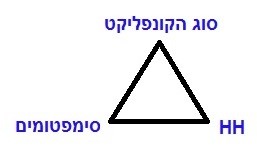

אפשר לראות מודל זה כמשולש שניתן להיכנס אליו מכל אחת מהפינות ולדעת לפי המידע של פינה אחת מה אמור להיות בשתי הפינות האחרות:

- לפי מיקום ה-HH במוח ניתן לדעת מה היה סוג הטראומה (או “הקונפליקט הביולוגי” כפי שזה נקרא כיום ברפואה החדשה) והיכן צפויים להופיע בגוף תסמיני המחלה.

- לפי תסמיני המחלה ומיקומם בגוף ניתן לדעת מה היה הקונפליקט שגרם למחלה והיכן יופיע ה-HH בצילום CT של המוח.

- לפי סוג הקונפליקט שהאדם חווה ניתן לדעת מהי המחלה שצפויה להתפתח בגופו והיכן יופיע ה-HH בצילום CT של המוח.

ההצלבה של סוג הקונפליקט↔HH↔הסימפטומים היא כנראה המודל הרפואי היחידי הקיים כיום שבעזרתו ניתן לגלות ולהוכיח בצורה מדעית את הגורם לכל סוג של מחלה.במשך חייו הצטברו אצל ד”ר האמר מעל 50,000 מקרים מתועדים.על בסיס ממצאיו הוא פרסם טבלאות והסברים מפורטים המאפשרים לרופאים ומטפלים שלמדו את הרפואה החדשה לדעת במרבית המקרים מה היה גורם המחלה אצל המטופל הספציפי, גם בלי צורך לעשות לו צילום CT של המוח.